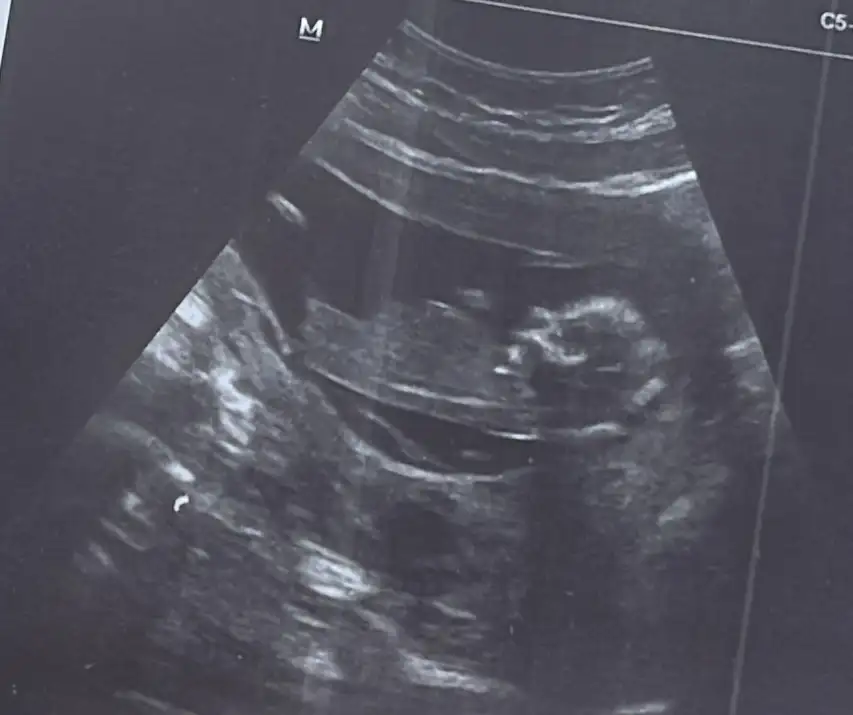

bize de tahminde bulunur musunz doktorumuz tahmin etti ama net değil dedi baska bı doktora gittik o da belli değil daha dedi

Benimkine de tahminde bulunabilir misiniz rica etsemKesenin şekli cnm

Kız benceEki Görüntüle 3501296 banada bakarmisiniz burda 12 haftalik 15 haftalik oldu daha belli degil

Benim için de tahminde bulunabilir misiniz cokk teşekkürler